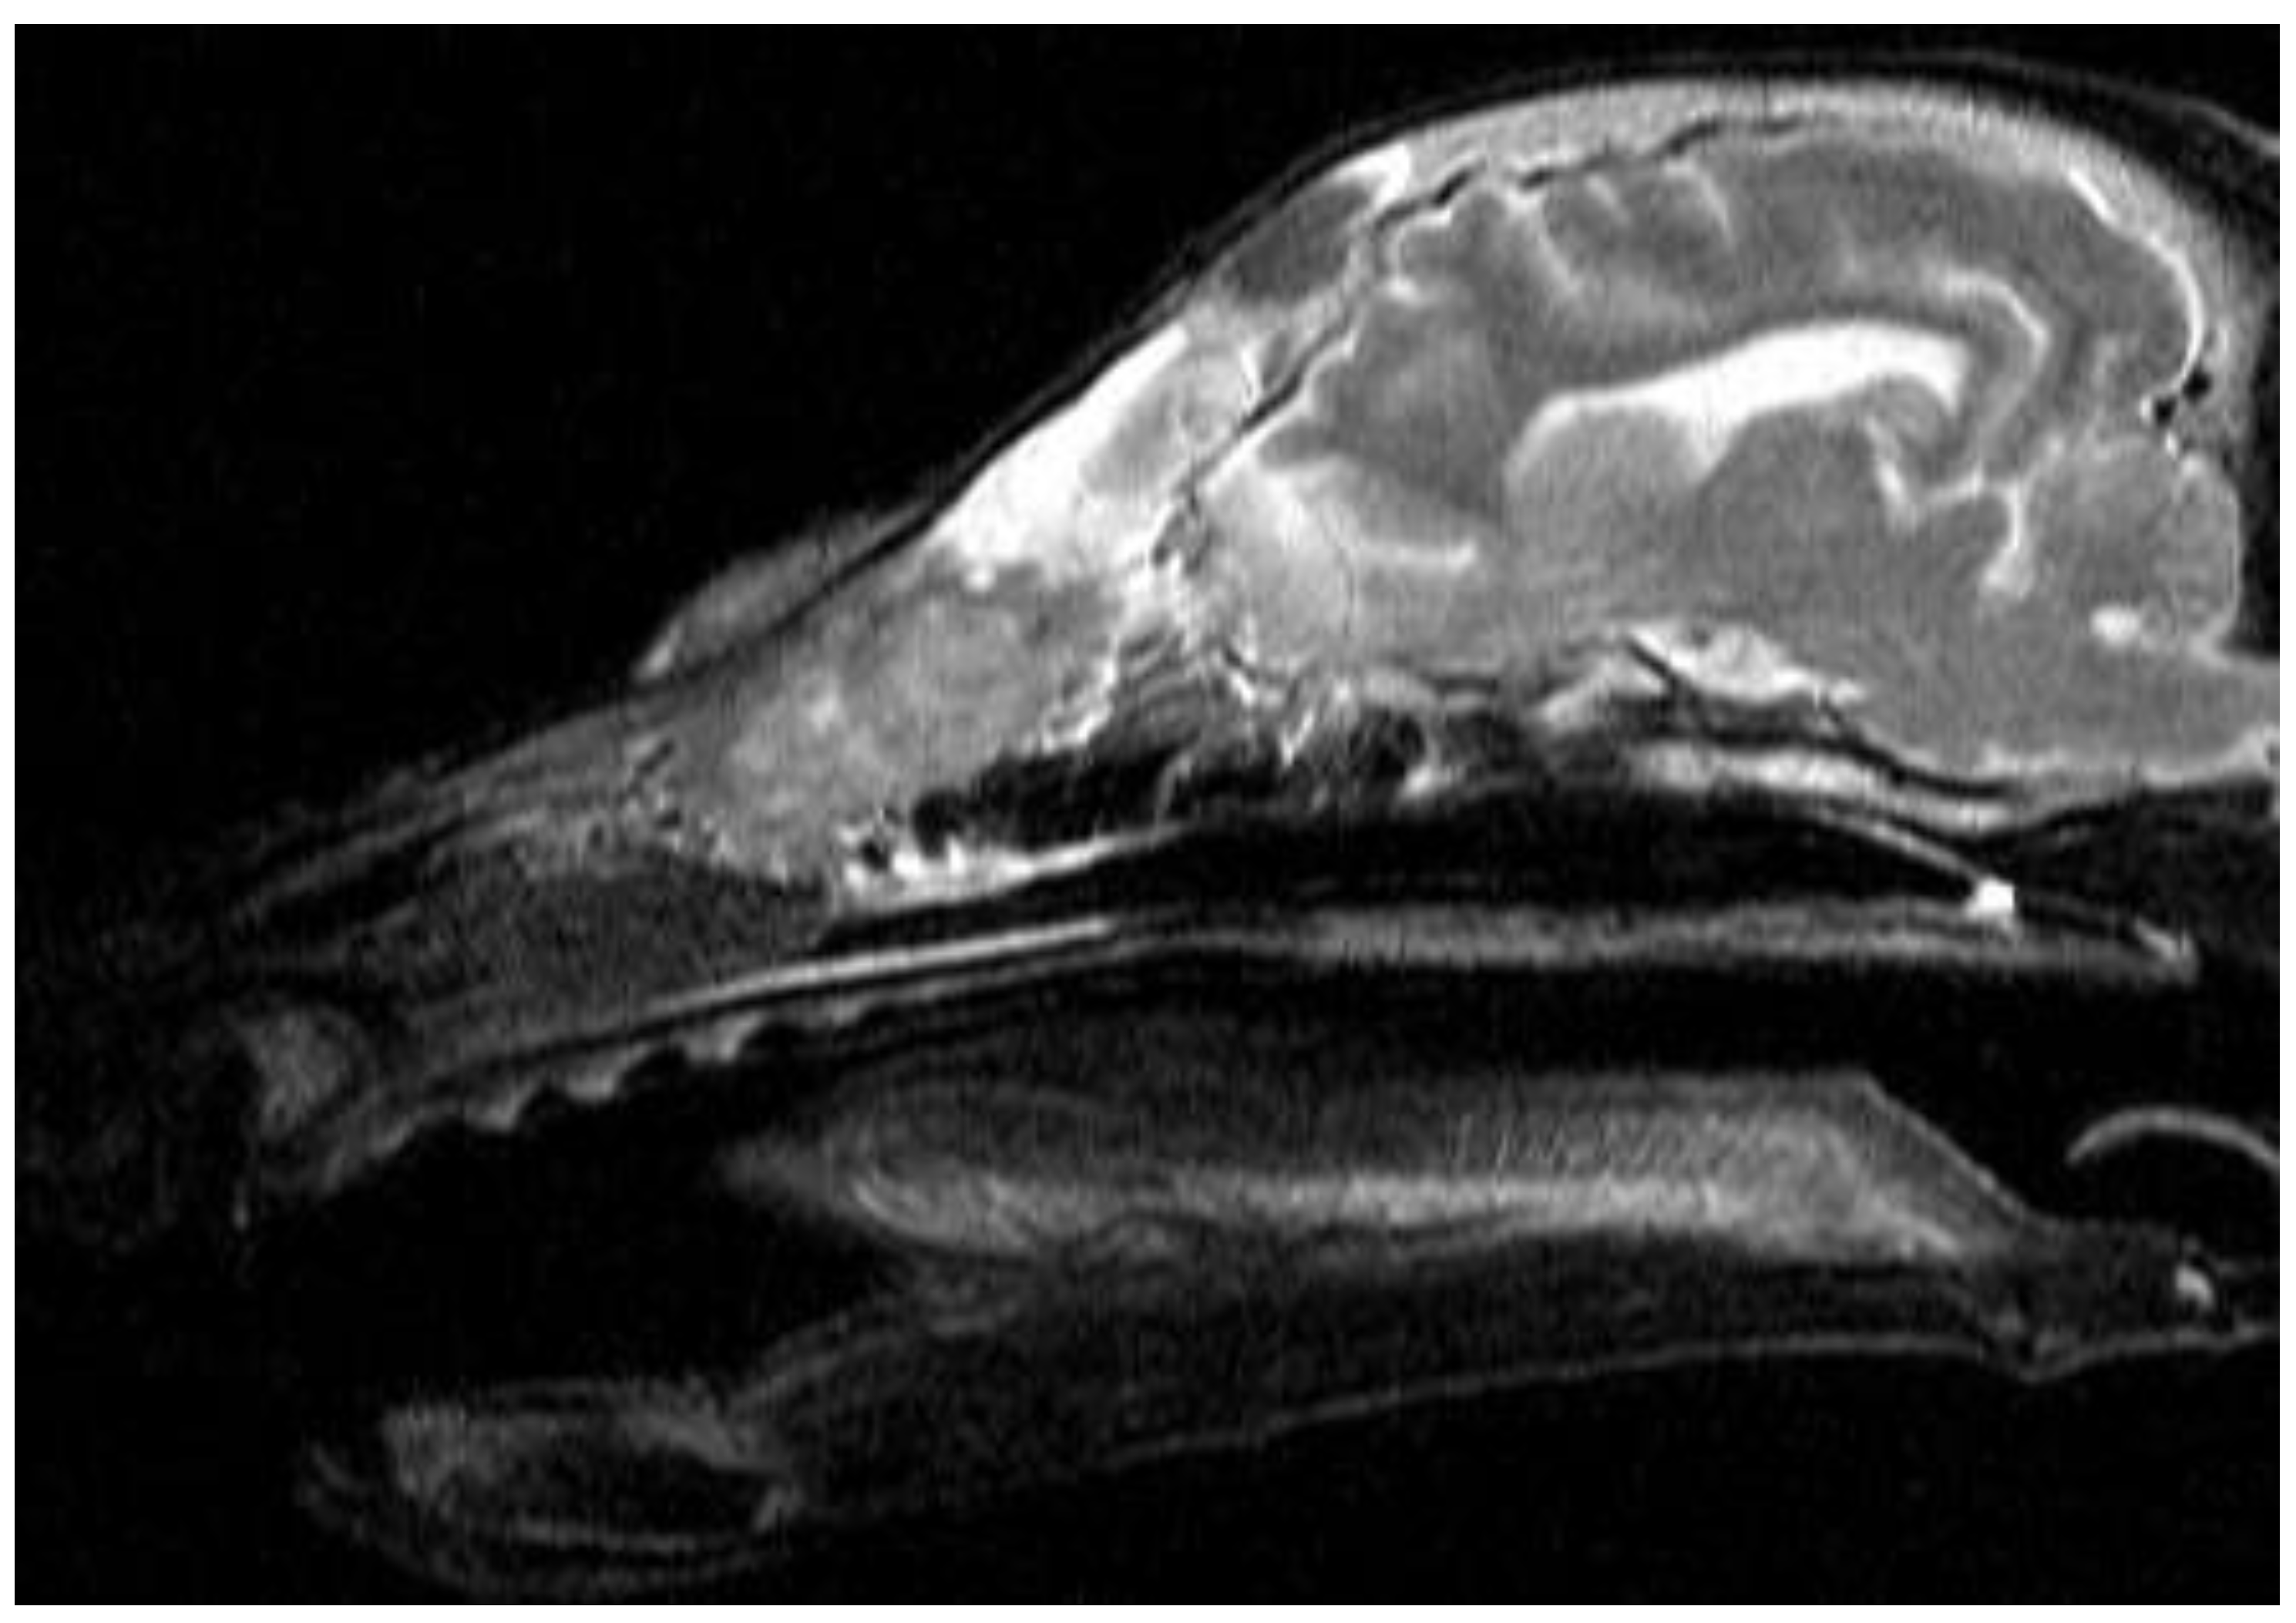

Figure A1. Dachshund dog, 13 years old, 9 kg. T2-VI mode sagittal plane. Heterogeneous hyperintense signal from the nasal cavity, areas of the ethmoid bone and frontal sinus – neoplasm.